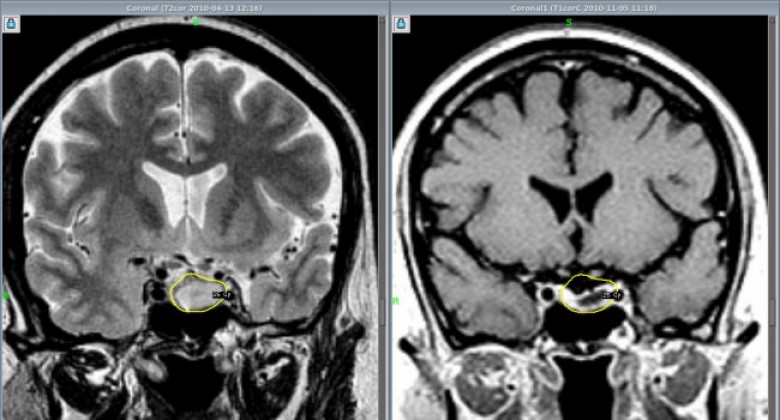

ОБЩЕСТВОАденома гипофиза – это доброкачественное новообразование, которое может крайне негативно сказываться на качестве жизни, вызывая нарушения со стороны эндокринной системы, а также нарушения зрения.

До недавних пор такие новообразования в МЦ «Астхик» удаляли с применением хирургического микроскопа. Теперь в медцентре внедряют и другой метод удаления аденом гипофиза – с помощью эндоскопа. Этот метод до недавних пор в Армении не применялся, и обучать ему специалистов в рамках одного из проектов благотворительного фонда «Вива» будет известный нейрохирург Вилен Азизян (Россия). В медицинском центре «Астхик» он уже провел три операции по удалению аденом гипофиза. Ассистировали ему армянские специалисты, которые в дальнейшем научатся проводить такие операции самостоятельно.

Аветис Киракосян, руководитель отделения нейрохирургии МЦ «Астхик», рассказал журналистам о том, что для внедрения эндоскопического метода удаления опухолей гипофиза был выбран медцентр «Астхик», так как материально-техническая база центра соответствует всем требованиям к проведению этих операций. Специалист уверен, что если в центре будут применяться оба метода, это поможет достигать более значительных результатов.

«В зарубежных медицинских центрах, где я проходил переподготовку, совмещают микроскопический и эндоскопический методы. После работы микроскопом проводят ревизию операционной области с помощью эндоскопа – без лишних разрезов через нос пациента вводят эндоскоп с камерой, осматривают область, иногда можно бывает обнаружить небольшие куски, которые остались вне поля зрения микроскопа, а эндоскоп может обеспечить более широкое поле зрения», - объяснил специалист.

По его словам, эндоскопическое удаление аденом гипофиза считается менее травматичным и менее инвазивным, чем микроскопическое удаление. Так или иначе, некоторым пациентам может потребоваться один из методов, некоторым – сразу оба, поэтому будет большим плюсом, если хирург будет одинаково хорошо владеть обоими методами.